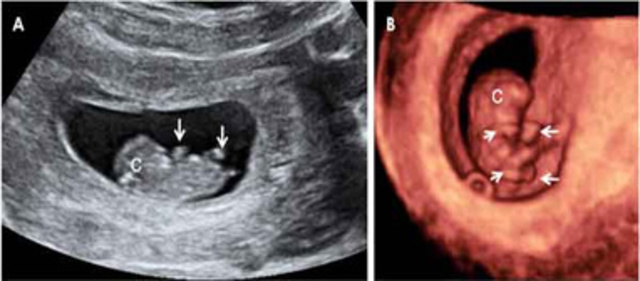

Aparece el cordón umbilical porque el bebé empieza a separarse de las paredes del saco gestacional; La cara del bebé toma más definición esta semana y pueden verse una perforación para la boca y muescas diminutas de nariz y esbozos de las orejas. Se hacen evidentes las primeras manifestaciones del desarrollo cerebral mediante la formación de las vesículas cerebrales primitivas.

El cerebro emite sus primeras ondas cerebrales detectables. Son evidentes los brotes de los cuatro miembros con mejor definición de los rayos digitales (el inicio del desarrollo de los dedos de los pies y manos) . Las muñecas, los codos y los tobillos son claramente visibles y los párpados del bebé se comienzan a formar. Las orejas, el labio superior y la punta de la nariz se hacen reconocibles, el corazón adquiere sus 4 cavidades y se inicia el desarrollo del sentido del olfato.